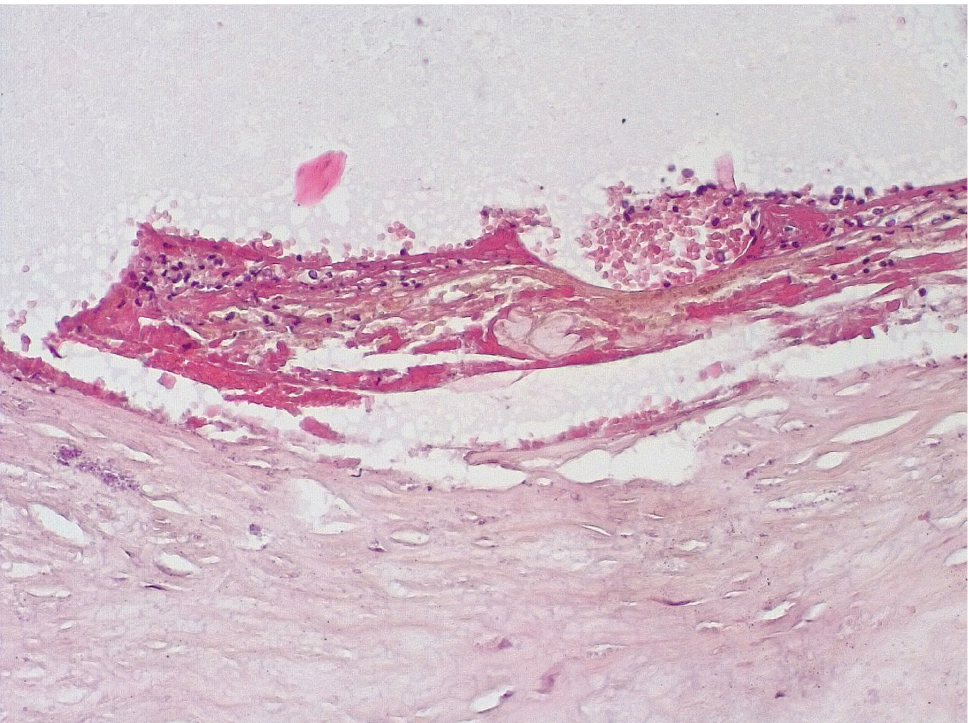

Позднее, спустя 3–7 суток после стентирования КА в просветах имелись пристеночные смешанные фибриново-лейкоцитарные тромбы, которые могли служить источником развития тромбоэмболических осложнений мелких дистальных ветвей коронарного кровотока и развитием острого инфаркта миокарда (рис. 4).

Рис. 4. Пристеночный смешанный (фибриново-лейкоцитарный) тромб в просвете КА (3–7-е сутки). Окраска гематоксилином-эозином. Ув. ×200